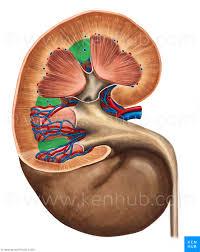

Calyx (of the kidney)

Medullary pyramids

Renal capsule

Renal columns

Renal cortex

Renal medulla

Renal Pelvis